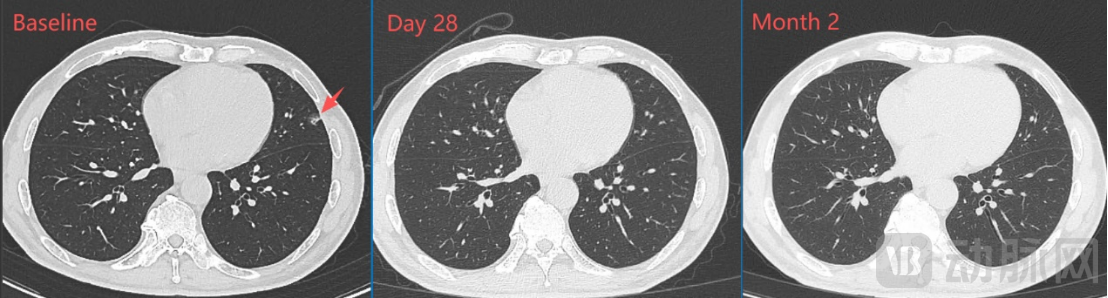

一个月的影像学检查显示:肝门区靶病灶明显缩小、肺部靶病灶基本完全消失,靶病灶直径之和从基线期的67mm缩小至43mm(下降35.8%),按RECIST1.1标准评估已达到部分缓解(PR);两个月的影像学检查显示:肿瘤病灶维持PR,且靶病灶直径之和进一步缩小至35mm(下降47.8%)。